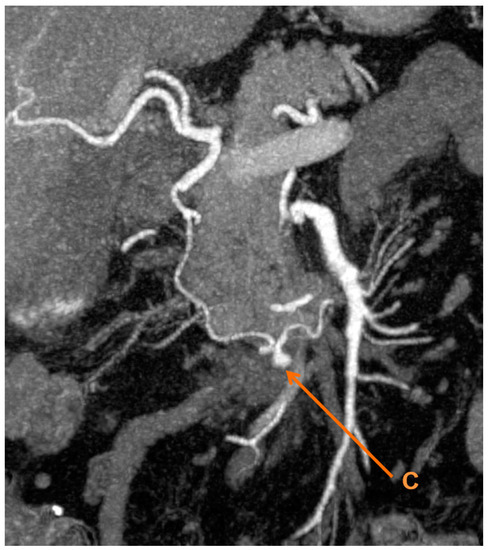

There was a 6 mm inferior pancreaticoduodenal artery pseudoaneurysm, which was not apparent on previous imaging (Figure 2). There was mild stenosis involving the origin of the coeliac axis. Additional observations included: Haematoma around D3 and a gastric outlet obstruction resolving; gallstones within a distended mildly thick-walled gallbladder, with no surrounding inflammatory changes; no biliary dilatation; normal pancreas; a small periampullary diverticulum; generalised atherosclerosis; moderate sigmoid diverticulosis with scattered diverticulae throughout the rest of the colon.

Figure 2.

3D maximum intensity projection reconstruction of the computed tomography showing (C) a pseudoaneurysm of the inferior pancreaticoduodenal artery.